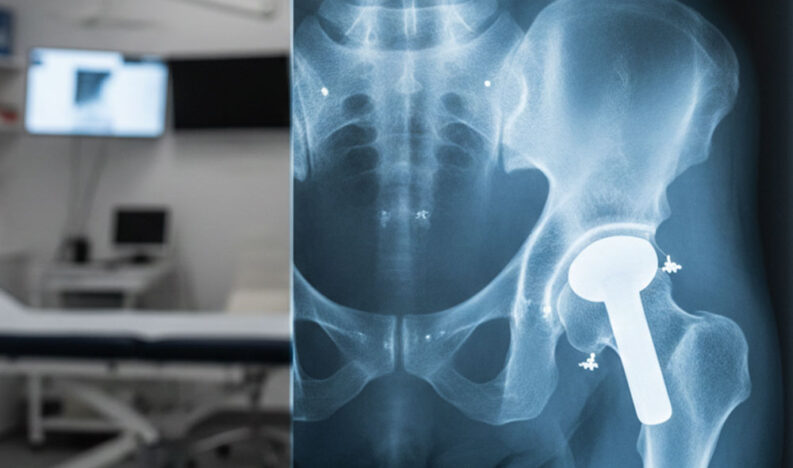

Total Hip Replacement Surgery